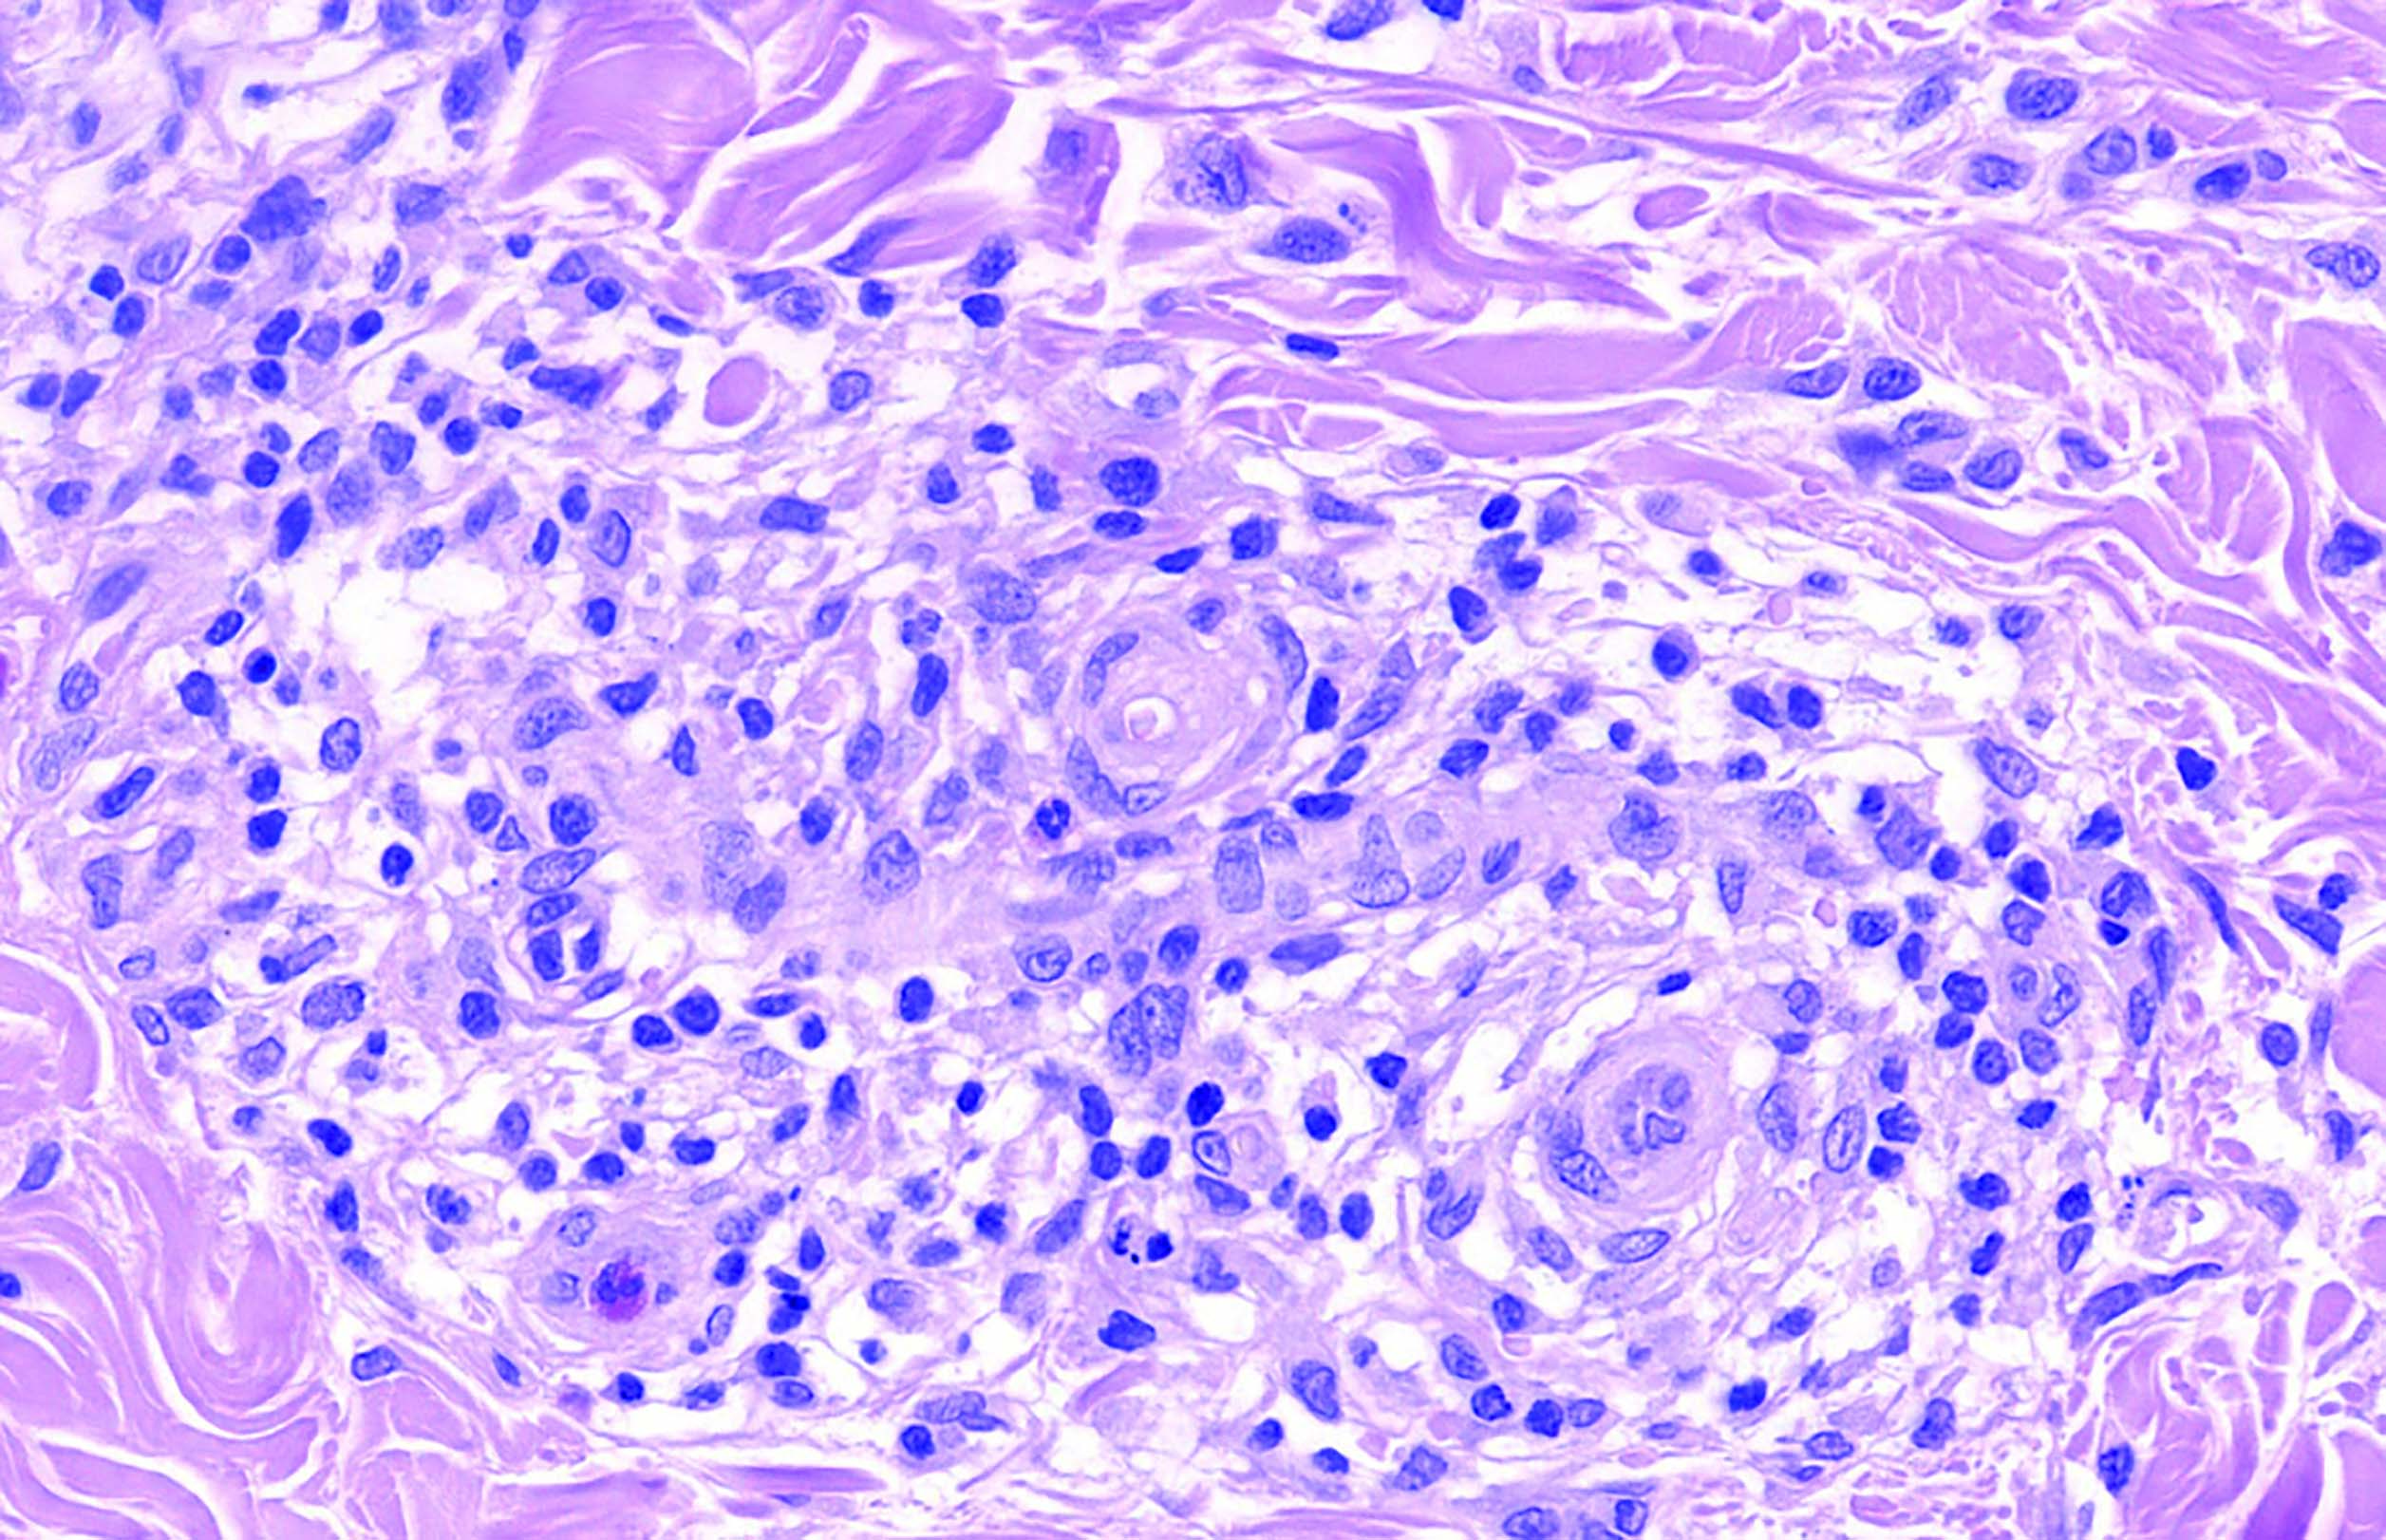

Рис. 4. Опухолевые клетки среднего размера с овальными ядрами, 1–2 мелкими ядрышками, амфофильной цитоплазмой. В некоторых клетках опухоли можно различить складку ядерной мембраны. Среди них рассеяны немногочисленные лимфоциты, гистиоциты и малочисленные эозинофильные гранулоциты. Окраска гематоксилином и эозином (ув. х600)

Fig. 4. Medium-sized tumor cells with oval nuclei, 1–2 small nucleoli, amphophilic cytoplasm. In some tumor cells, a fold of the nuclear membrane can be distinguished. A few lymphocytes, histiocytes, and eosinophilic granulocytes are scattered among them. Staining by hematoxilyn and eosin, x600